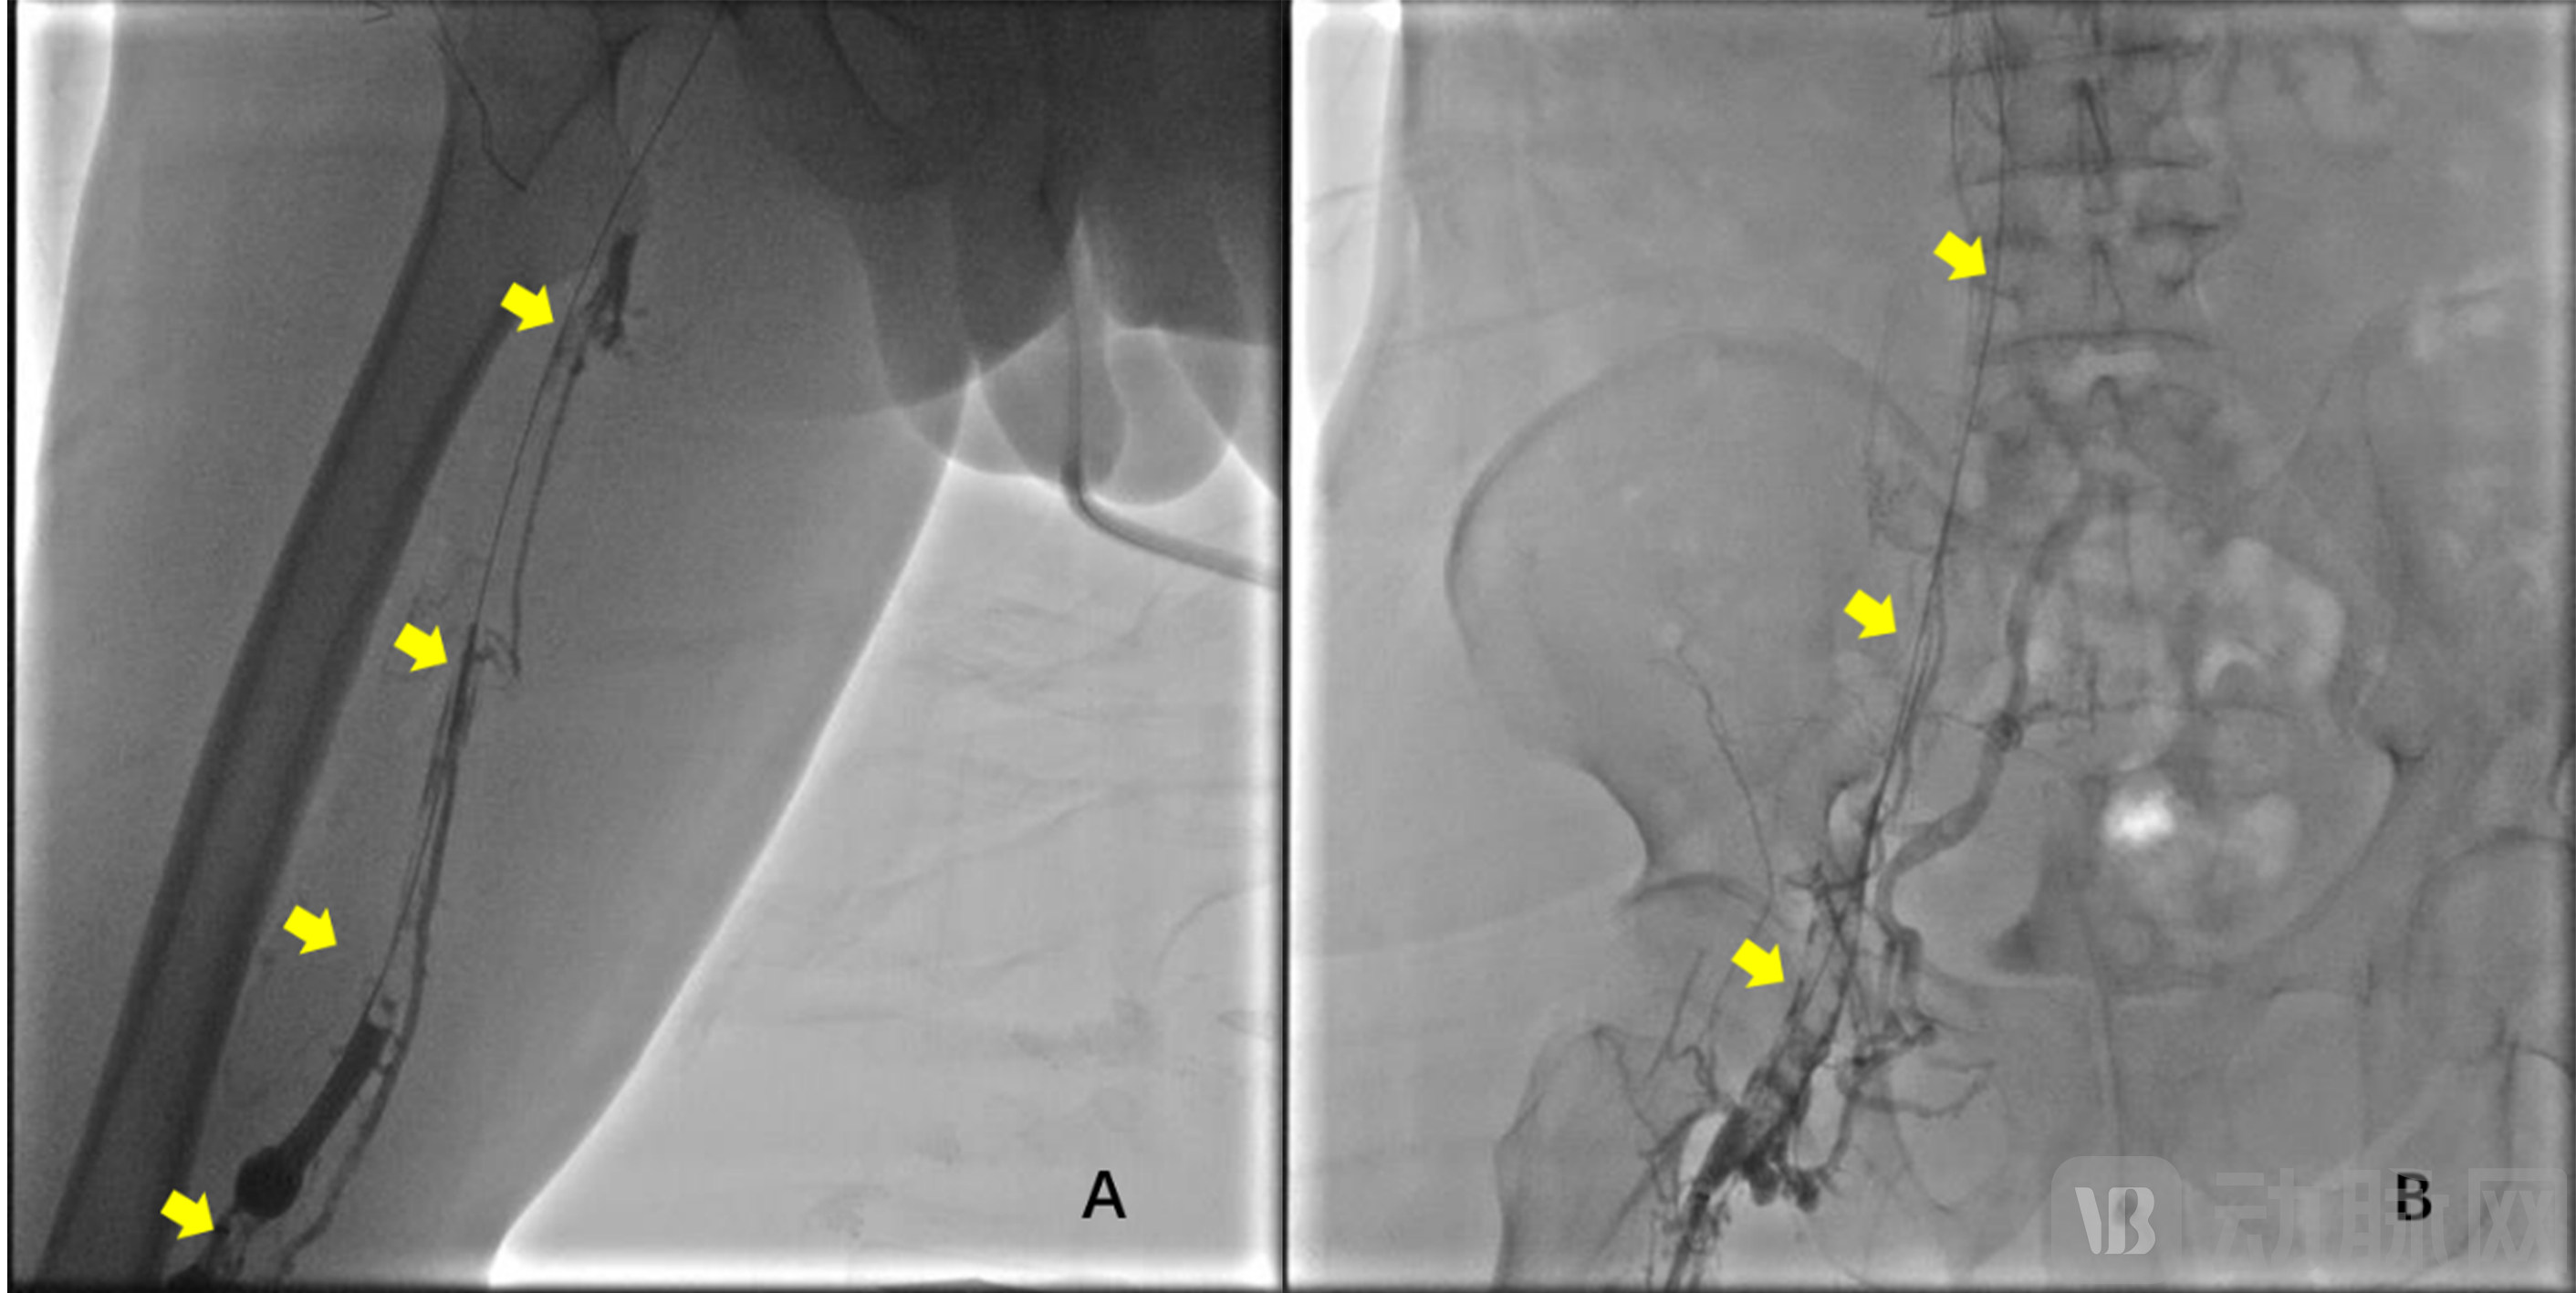

2023年8月16日,赣州市人民医院(南方医院赣州医院)血管外科叶波教授及其团队,应用“荷声”超声辅助溶栓导管为一例下肢深静脉血栓形成的中年男性患者成功进行了微创除栓治疗,成功完成了“荷声”超声辅助溶栓导管首例临床FIM试验,具备重大里程碑意义。患者右下肢肿胀十天余,加重伴小腿水泡形成5天。彩超和静脉造影均显示:下腔静脉下段、右髂股腘静脉全程血栓,管腔完全闭塞(图2)。

图2 A:右腘静脉、股静脉全程血栓(黄箭头)、血流阻塞

B:右股总、髂外、髂总静脉和滤器下方下腔静脉全程血栓(黄箭头)、血流阻塞

术中经颈静脉放置下腔静脉滤器后,穿刺右侧腘静脉,导丝和导管配合通过血栓,置入“荷声超声辅助溶栓导管”,治疗工作时间15min后,造影显示:右腘静脉、股浅静脉、股总静脉、髂外静脉中远段血栓清除率达到90%以上,正向血流恢复(图3A);治疗工作时间30min后,髂腔静脉血栓进一步溶解,右髂外静脉血栓清除率近100%(黄箭头),右髂总静脉和下腔静脉血栓清除率近50%(绿箭头),正向血流恢复(图3B)。治疗工作时间120min后,静脉造影证实,髂总静脉、下腔静脉血栓清除,血流通畅,仅残留右髂总静脉局限性残余狭窄(长度小于5mm),最终以球囊扩张右髂总静脉残余狭窄后,成功拔除滤器(图3B)。治疗过程中患者无不适主诉,术后患者肢体肿胀迅速缓解,腿围缩小,康复出院。